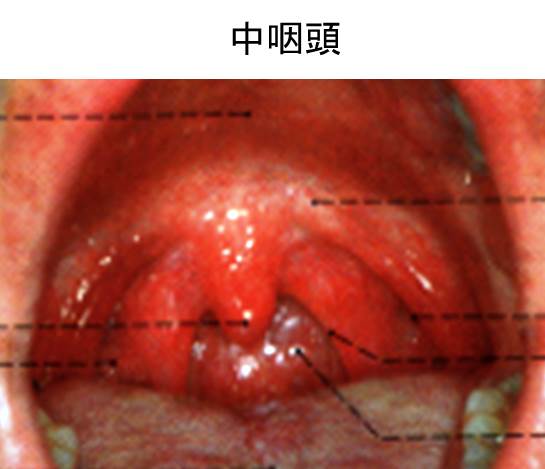

中咽頭癌 その38 定期受診 ct撮影 こんばんは 世の中gwですが今年はコロナのせいで出かけられないし病院通いでもまぁいいかって感じです.

中咽頭癌 ct. 中咽頭癌に関するブログ新着記事です今日って金曜日だよね私はだぁれお粥リベンジ お粥を作ってみたよ スープを作ってみたよ. Ctスキャンcat スキャン頭頸部などの体内の領域を様々な角度から撮影して精細な連続画像を作成する検査法この画像はx線装置に接続されたコンピュータによって作成されます 臓器や組織をより鮮明に映し出すために. 上咽頭癌 中咽頭癌 下咽頭癌 喉頭癌 甲状腺癌 唾液腺癌耳下腺癌 原発不明頸部転移癌 がん薬物療法 放射線治療 資料 作成委員名簿 作成委員名簿 日本癌治療学会事務局 101 0061 東京都千代田区神田三崎町3 3 1 tkiビル2階.

中咽頭がん扁平上皮がんサバイバー三枝幹弥さんへのインタビューです 厳しいガン体験が教えてくれたこと仕事家族東京マラソン 基本情報 名前 三枝幹弥さん 年代性別 40代男性 病名 中咽頭がん扁平上皮癌 進行ステージ ステージⅳa 治療期間 2010年11月.

中咽頭癌 扁平上皮癌 Stage 放射線 サイバーナイフ 後の残存腫瘍の治療